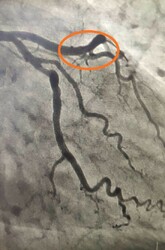

Операция проводилась эндоваскулярным методом, под контролем современной ангиографической установки, с помощью введения контрастного вещества. Непосредственно вмешательство проводил специалист по рентгенхирургическим методам лечения и диагностики БГКБ Сергей Полянский.

«Через лучевую артерию провели диагностическую ангиографию, ввели проводник со всеми вспомогательными инструментами до восходящей аорты. Выявили суженный участок одного из сосудов, подвели баллон со стентом и установили стент в нужном месте», – говорит Сергей Полянский.